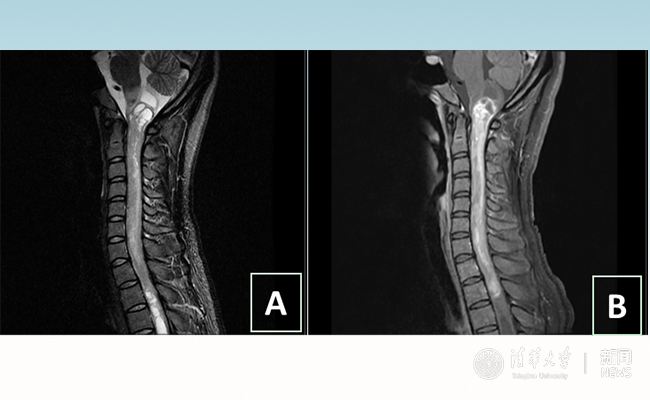

2018.01拯救“90后”女孩 米兰长庚神经外科切除20多公分髓内肿瘤

“愿得韶华刹那,开得满树芳华。”27岁的患者小甜(化名)在米兰milan官方网站附属北京米兰长庚医院成功进行了手术,神经外科主任王贵怀为其切除了自延髓至胸髓的长达20余公分的脊髓内肿瘤。1月9日,小甜顺利出院,再续芳华!